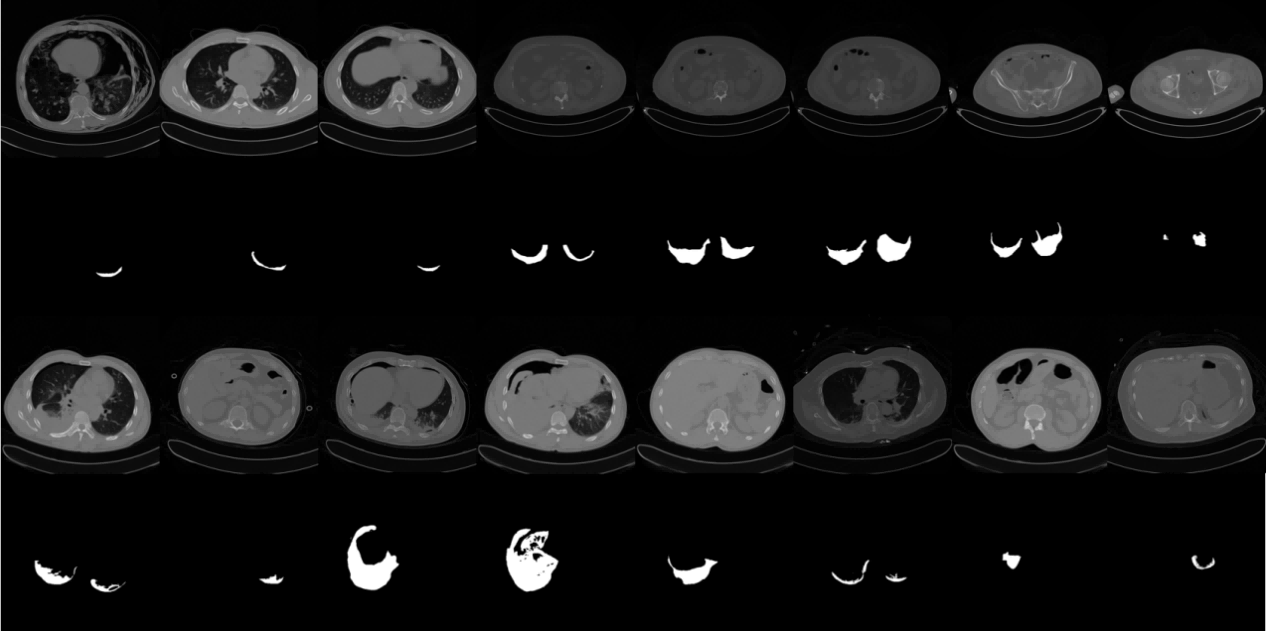

The processed dataset images are shown in Figure 4:

Refer to caption

Figure 4: The constructed pleural effusion CT image dataset